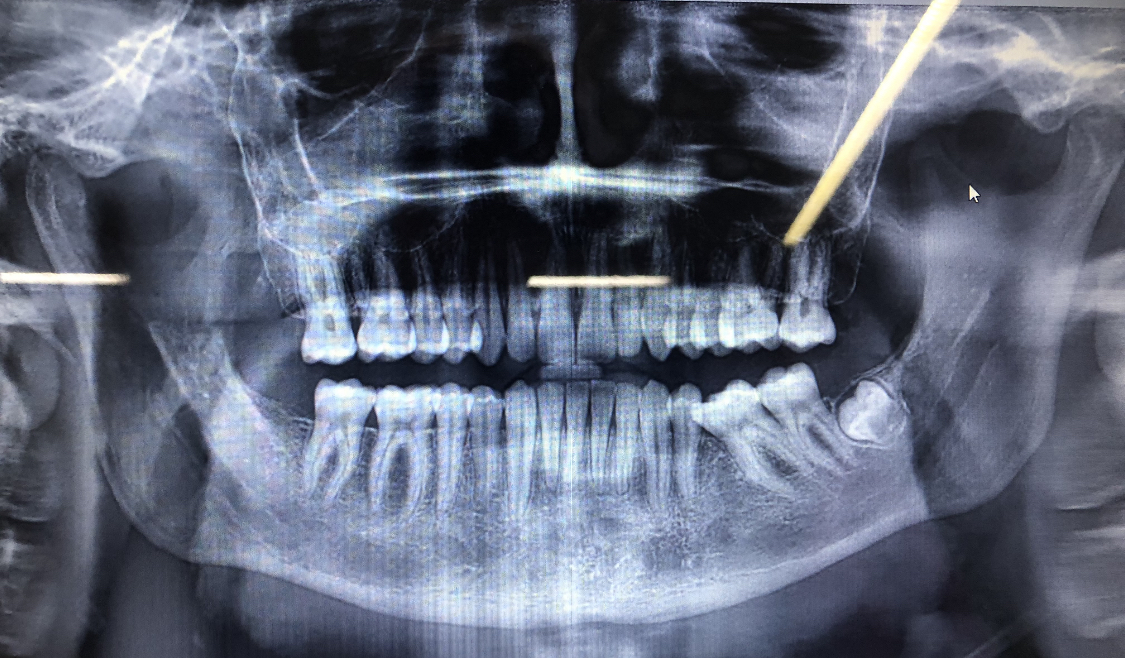

Holy shit just got a scan thing and my teeth are fucked like Richard Ramirez teezh

The right side is so fucked Like I Miss one tooth (premolar) dont ask me why and I only have one wisdom teeth for some reason the other 3 are not there idk why this hoe said cuz genes bro wdym genes my whole family literally has 4 wisdom teeths dumb bitch man